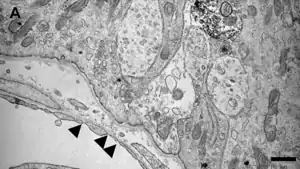

[[File:CVO Estruct.jpg|400px|alt={{{Alt|MVs= microvaso. Procesos celulares de las NSC (flechas sólidas). Asteriscos: dendritas similares a astrocitos/tanicitos. Microscopio electrónico]]

MVs= microvaso. Procesos celulares de las NSC (flechas sólidas). Asteriscos: dendritas similares a astrocitos/tanicitos. Microscopio electrónico

La microscopía electrónica ha demostrado que los CVO-Sn, presentan poros en el endotelio de 30 a 80 nanómetros (nm) de diámetro. Estas fenestraciones se encuentran cubiertas por prolongaciones de las células perivasculares similares a pericitos/tanicitos.[5]